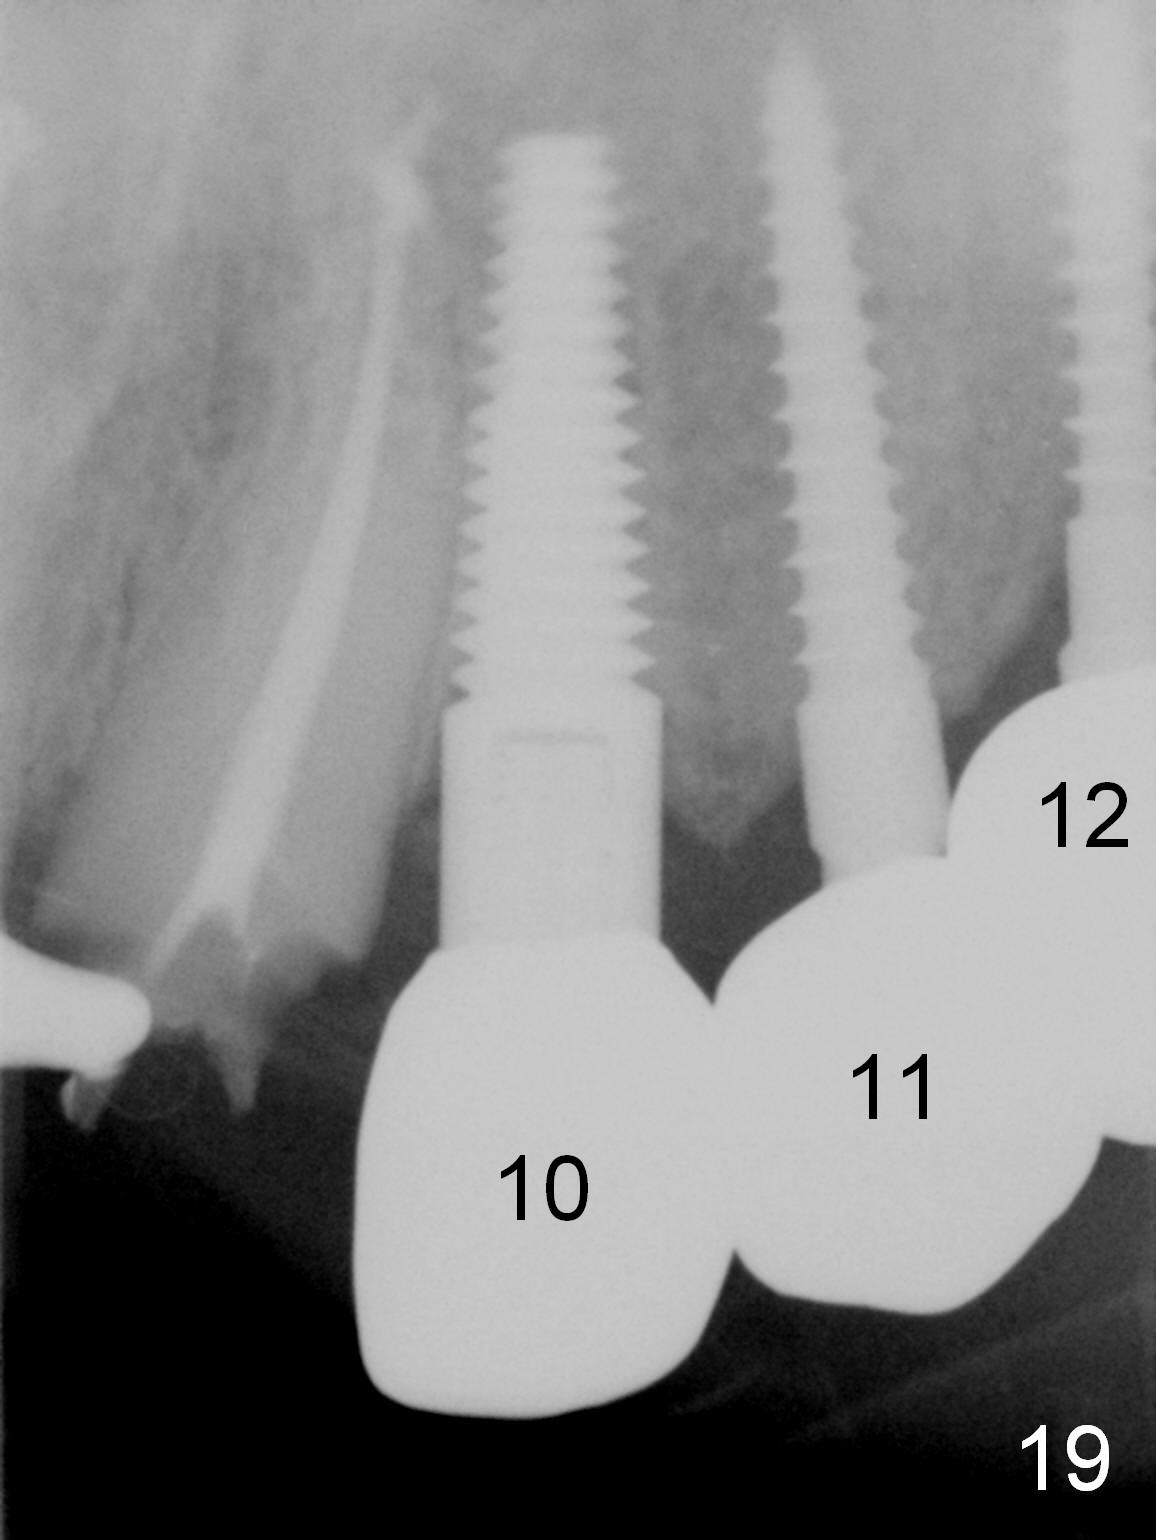

Six months post cementation, the tooth #9 becomes symptomatic.  Is it possible that the implant at #10 is too close to the root of #9?  It is asymptomatic after pulpotomy, but the tooth fractures equi/supragingivally.  Two PAs taken while RCT show osteointegration at #10-12 (Fig.18,19).  While the bone density increases at #10 regular implant, there is minimal bone loss around the 1-piece implants 13 months post cementation (18 months postop, Fig.20,21).  The gingiva remains healthy 19 months post cementation (Fig.22).  76岁病人突然打电话说一个植牙牙冠松动,其实9号牙(自然牙)折裂,6,10-13号牙植牙好像没有骨质吸收(图二十三至二十五),10-13牙位牙龈健康(图二十六,行使功能五年)。9号牙牙冠重新粘固后,显示前牙深覆合,深覆盖(图二十七,二十八)。如果再次脱落需要植牙,选择一段式有助于植入和修复,因为植体和基台直径小。两段式植牙相对基台直径至少4,或者4.5毫米,前牙修复显得笨重。由于9,10牙根和植体接近,9号牙植体需要偏小而长,3x14或者15毫米(图二十九)。